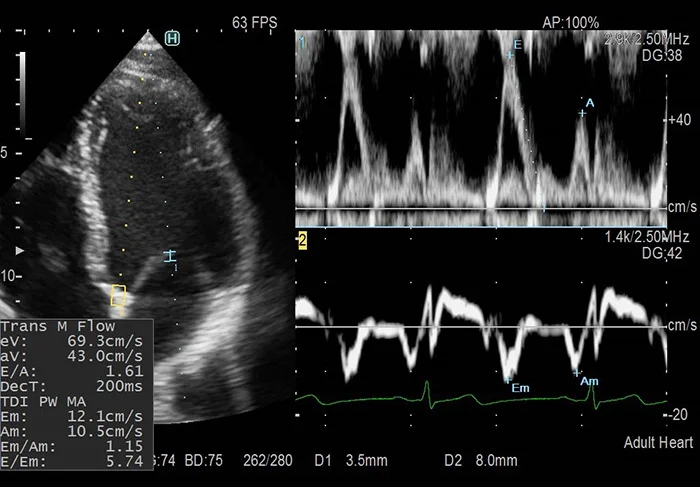

Интеллектуальный двойной допплер

Функция iDGD позволяет получить соотношение E/e` всего за несколько секунд! Возможна автоматическая установка обоих контрольных объёмов для одновременного получения двух спектров за одно сердечное сокращение, а также автоматическое определение пиков сигналов для измерения. Более того, программа может самостоятельно выделить стабильный R-R-интервал по кривой ЭКГ, что чрезвычайно полезно при исследовании пациентов с аритмией.